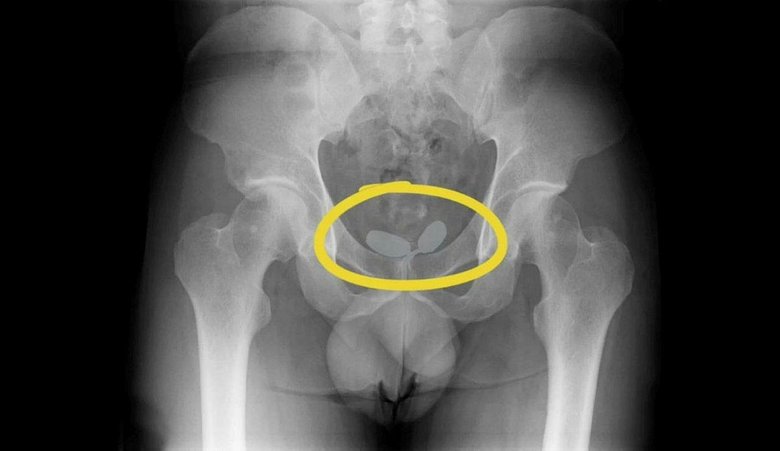

Şüphelilerin yapılan iç beden muayenesinde, prezervatifler içinde yutulmuş ve vücut boşluklarına gizlenmiş halde 21,19 gram eroin, 12,70 gram kokain, 7,76 gram metamfetamin ve 7 sentetik hap ele geçirildi. Gözaltına alınan şüpheliler, polisteki işlemlerinin ardından bugün adliyeye sevk edildi.